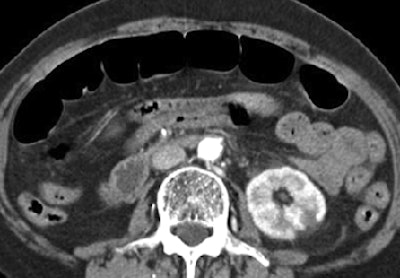

| In a 56-year-old man with acute mesenteric ischemia, neither emboli nor thrombi are definitively shown on axial arterial-phase CT (above). However, oblique coronal plane of volume-rendered image (below) shows large embolus (thick arrow) and extensive vascular occlusion (arrowheads) along the superior mesenteric artery and its branches, with multifocal renal infarction (thin arrows). Because this patient suffered from long-standing severe heart failure, mesenteric ischemia was conservatively managed with anticoagulant drugs. Images republished with permission of the American Roentgen Ray Society from AJR; 2006; 187: 1212-1221. |